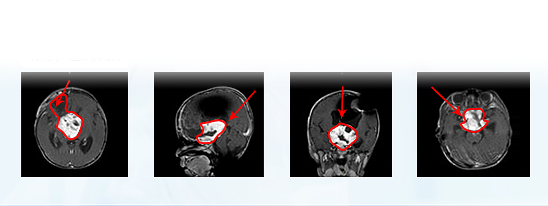

术前MR

国内一次手术后